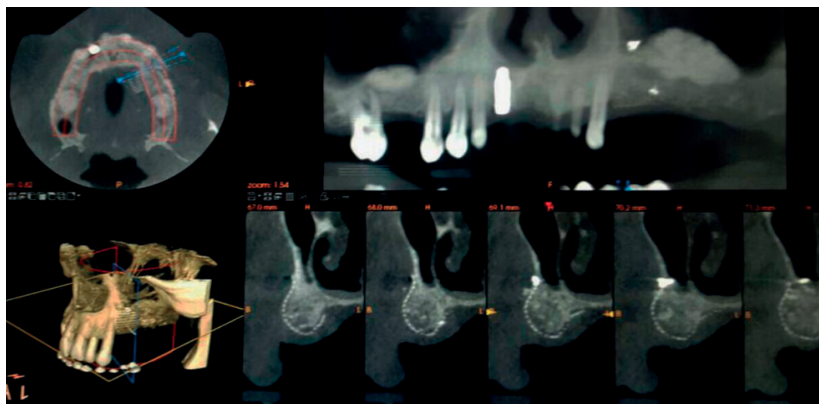

A los seis meses se realiza al paciente una nueva tomografía computerizada, se efectúan nuevas mediciones y se prepara la reentrada quirúrgica para la segunda fase del tratamiento (Figura 7).

El tejido óseo neoformado muestra buenas dimensiones en altura y anchura, lo cual permitirá al clínico seleccionar los implantes adecuados (diámetro/longitud). Se observa que se ha logrado la consecución del objetivo principal del presente caso clínico, donde se partía de una situación inicial con 6 mm en altura y 4 mm de anchura de hueso maxilar remanente y se finaliza con un total de 12 mm de cresta ósea en altura y 10 mm en anchura regenerada con éxito (Figura 8).

Todo esto se confirma en el momento de la intervención para la inserción de los implantes (Figura 9). Tras la retirada de los tornillos de osteosíntesis y de la micromalla se observa un buen aislamiento de los tejidos blandos, así como un adecuado mantenimiento del espacio, consiguiendo una integridad estructural con un tejido óseo estable, sangrante y bien incorporado al tejido huésped. El hueso regenerado disponible, tras la exploración clínica, se corresponde con un hueso tipo D2 (criterio de calidad ósea de Misch 2009).